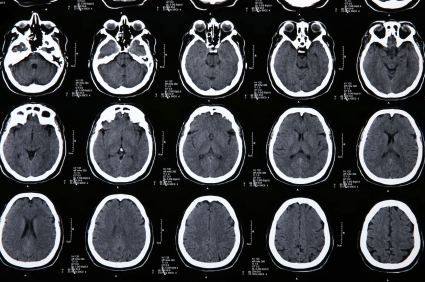

В связи с неспецифическими симптомами, необходимы анализы крови, а так же КТ и МРТ.

Медицинские процедуры, проводимые при заболевании энцефалит летне-осенний комариный (японский энцефалит): Клинический анализ крови, Биохимический анализ крови, Антитело, Спиральная компьютерная томография, Магнитно-резонансная томография